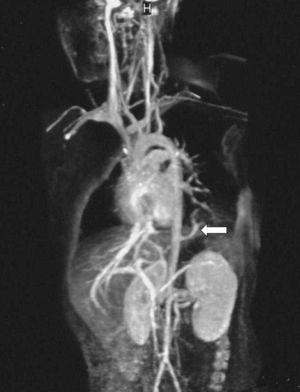

La radiografía de tórax, en inspiración y espiración (fig. 1), evidenció consolidación en lóbulo inferior izquierdo (asterisco), sin adenopatías mediastínicas ni signos de atrapamiento aéreo que sugirieran cuerpo extraño. En la TC torácica helicoidal sin contraste se confirmó una neumonía-atelectasia en lóbulo inferior izquierdo, sin derrame, adenopatías ni alteraciones en árbol traqueobronquial. El estudio de angio-RM reveló una consolidación en lóbulo inferior izquierdo, hacia la que se dirige un vaso (flecha) originado en la aorta torácica descendente, por encima del orificio diafragmático y que constituye un vaso arterial nutricio (fig. 2).

Figura 2. Angio-RM.